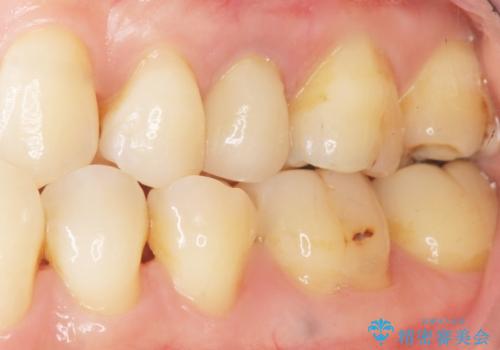

神経が死んで変色した歯 根管治療とオールセラミッククラウン